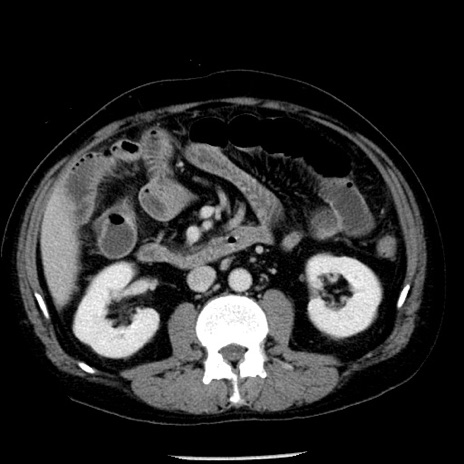

症例29(横断像)

【症例】40歳代男性

【現病歴】2日前から胃痛あり。徐々に周期的な激痛に変化した。本日になっても激痛があるため受診。

【身体所見】意識清明、BT 38-39℃台あり、腹部:膨満、やや硬、右下腹部に圧痛あり。

【データ】WBC 8500、CRP 23.26